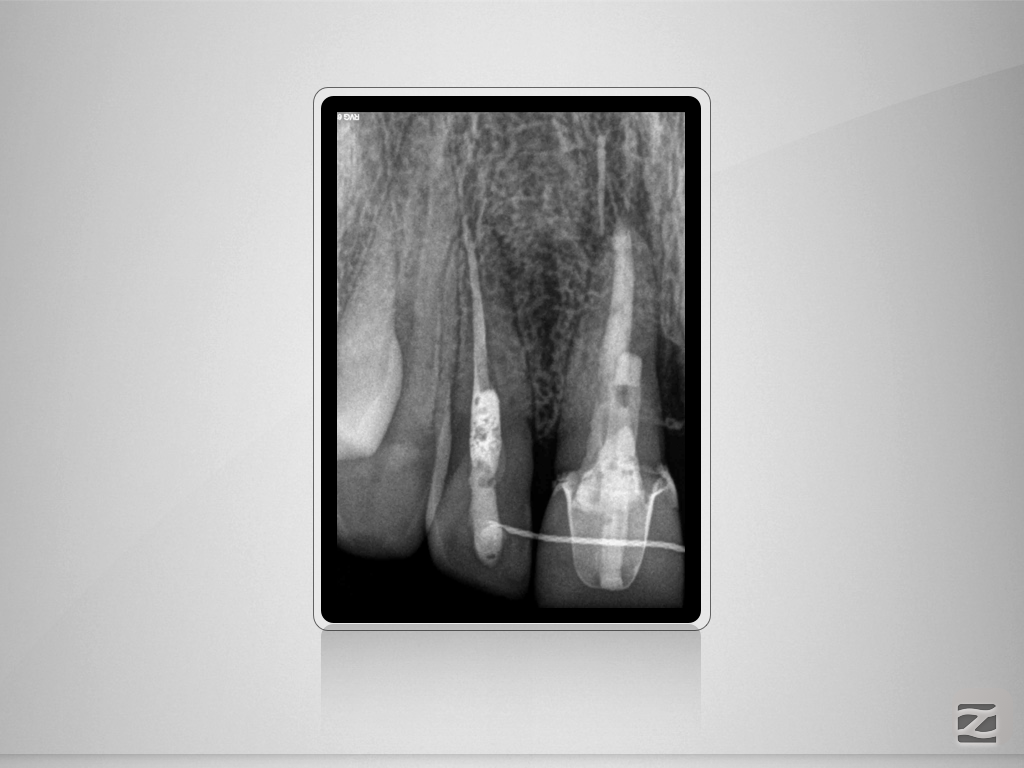

11D.001

An der Grenze …